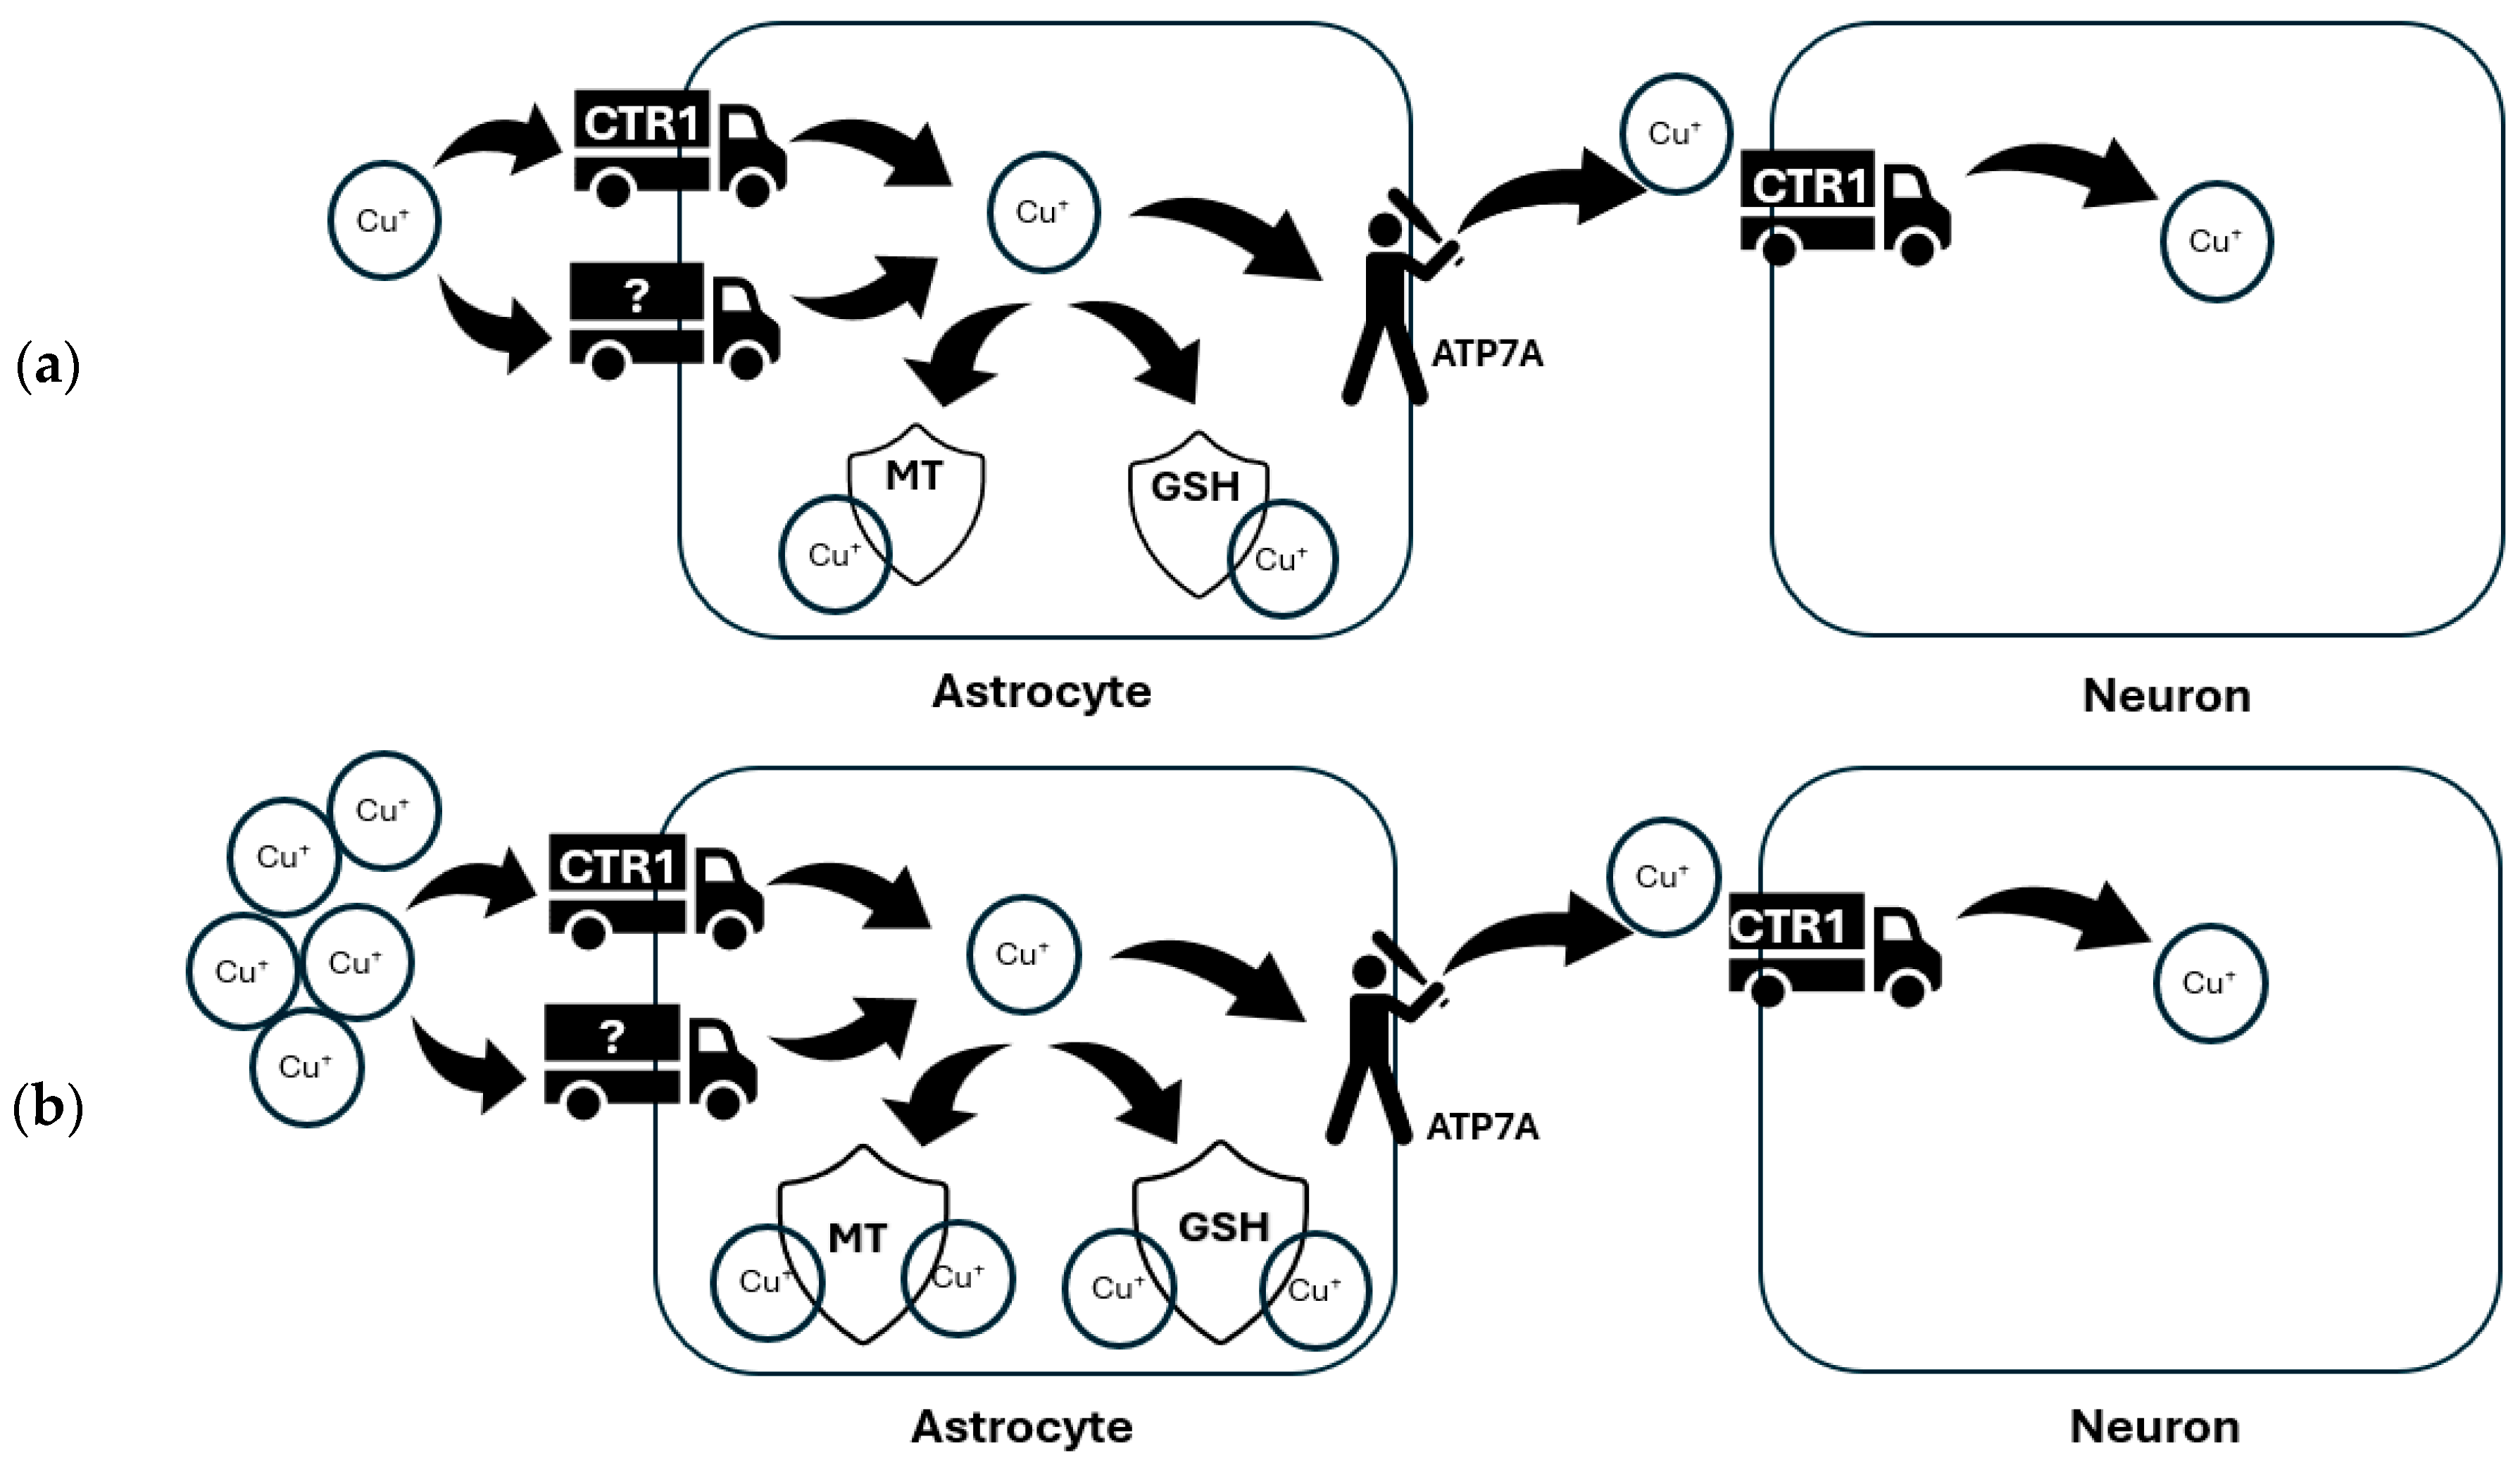

4.1. Glia in Brain Copper Homeostasis